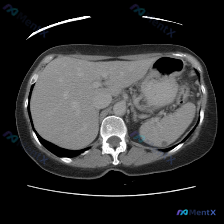

整理了一份腹部CT发现脾脏低密度结节的读片思路,分享给大家一起讨论。 先看影像表现(单幅平扫CT) - 肝脏:形态尚可,密度基本均匀,未见明显局灶性占位 - 脾脏:重点!脾脏大小形态正常,实质内靠近后缘可见一处圆形低密度小结节,边界尚清,密度接近水,无明显周围浸润或占位效应 - 其他:胃壁、脊柱、腹...